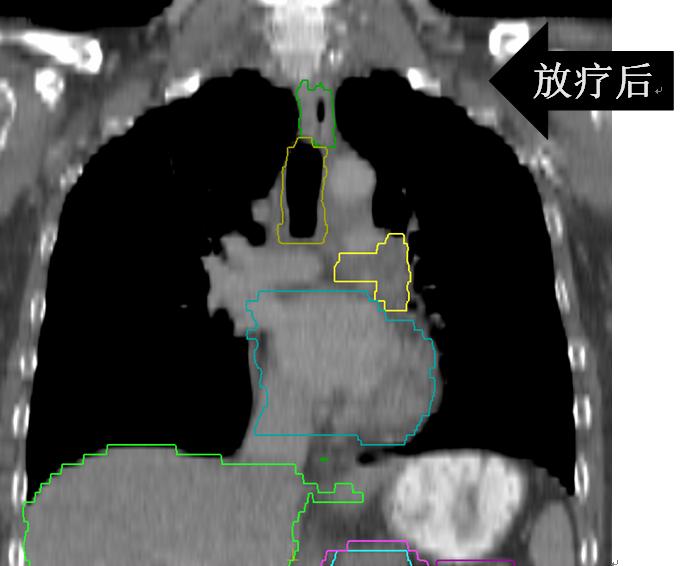

• (肺及纵隔病灶)iGTV1/GTV1/CTV1/70Gy/60Gy/50Gy/20F;

• (锁骨上病灶)GTV2/CTV2/60Gy/50Gy/20F。

放疗后患者咳嗽、咳痰、左肩背部疼痛、痰中带血、胸闷、气短完全缓解;继续于外院行综合治疗并定期随访观察。

有图有真相:放疗效果显著!是不是疗效好就应该损伤重呢?肺损伤?